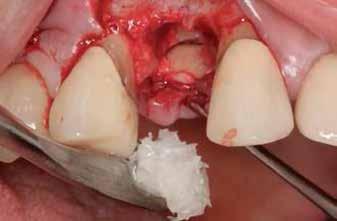

3. a–b ábrák: Fogeltávolítást követő alveolus prezerváció. – 4. a–b ábrák: Az implantátumok beültetése.

A fogak eltávolítása minimálinvazív módon történt, amelynek során a parodontális rostokat egy periotom segítségével átvágtuk, így lebenyes feltárásra nem volt szükség (3. a–b ábrák) . Az implantátumokat a frissen eltávolított fogak alveolusaiba ültettük be. A foghúzást követően minden alveolust alaposan ellenőriztünk az endodontiai, vagy parodontális eredetű gyulladásos szövetmaradványok eltávolítása érdekében, majd fiziológiás sóoldattal bőségesen átöblítettük. Megfelelő előfúrást követően a kerámiaimplantátumokat 30 fordulat/perc sebességgel és 35 Ncm behajtási nyomatékkal helyeztük be (4. a–b ábrák) . A réseket csontpótlóval töltöttük ki (Maxresorb ® 0,5–1,0 mm szemcseméret, 0,5 cm 3 térfogat, Straumann ®; 6. ábra ).